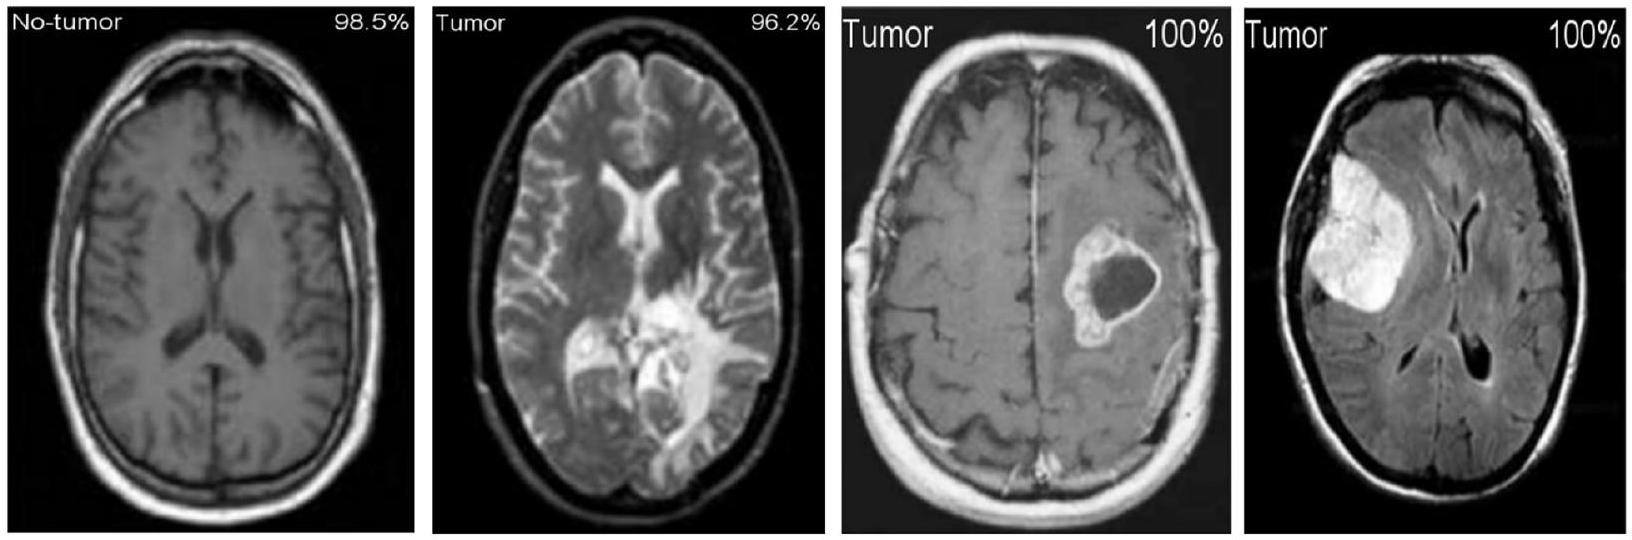

تظهر الشكل 11 نتائج التصنيف والاحتمالات المتوقعة لكل من الاختبارات الأربعة التي أجريت في وضع C-1. تم تنفيذ طريقة التحقق المتقاطع بخمسة أضعاف لـ

Figure 11 shows the results of the classification and the predicted probabilities for each of the four tests conducted in C-1 mode. Implementing the fivefold cross-validation method for the